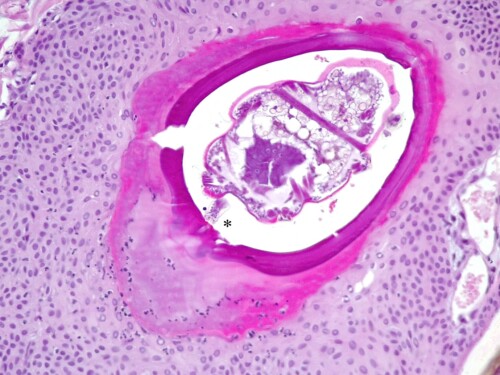

Photo 7 : vue à fort grossissement d’un follicule pileux lésionnel. Du centre vers la périphérie on observe bien l’acarien, tête en bas (on devine son rostre à l’extrémité inférieure), la paroi du kyste parasitaire minéralisée et ouverte sur l’extérieur, la kératine folliculaire rose vif, la gaine folliculaire hyperplasique. Notez le petit histosiphon du parasite planté dans la chambre de digestion présent sous lui (astérisque).

Crédit photo : LAPVSO

L’aspect histologique est tout à fait particulier, dominé par des lésions folliculaires intéressant la partie haute des follicules pileux. La paroi folliculaire montre une hyperplasie pseudo-épithéliomateuse et une hyperkératose trichilemmale (kératine homogène rose vif). La paroi est entourée à ce niveau par un derme oedémateux (pâle) et néovascularisé (riche en capillaires). Dans chaque follicule lésionnel on observe un parasite de type acarien dont la tête et le rostre sont dirigés vers le fond du follicule pileux. Une section permet de distinguer une pièce buccale du parasite, allongée en forme de paille, l’histosiphon, qui plonge dans un secteur liquéfié et inflammatoire de la gaine folliculaire sous-jacente, la chambre de digestion. Chaque parasite est entouré par une coque épaisse, vitreuse et plus ou moins basophile et minéralisée, ouverte sur l’extérieur avec des extrémités recourbées en « lyre ». A distance de ces follicules lésionnels le tégument ne montre pas de lésions significatives.

Le différentiel histologique est inexistant car cette présentation est pathognomonique d’une dermatose parasitaire unique en son genre chez le chien : la straelensiose. Il s’agit d’une folliculite proliférative due à une infestation folliculaire par des larves enkystées de l’acarien Straelensia cynotis.

La larve hexapode de Straelensia s’enkyste dans un follicule pileux dont elle est séparée par une coque en « U ». Elle se place la tête en bas, et une partie allongée de son rostre, l’histosiphon, vient se planter dans la paroi folliculaire. Sous l’effet probablement de substances sécrétées par l’acarien cette zone de paroi folliculaire se liquéfie en « chambre de digestion » permettant l’aspiration des sucs par le parasite. Le follicule pileux réagit en conséquence sous la forme d’une hyperplasie exubérante.